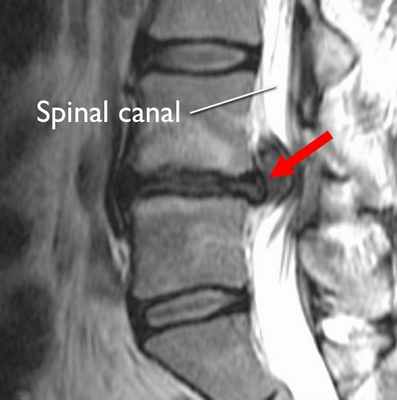

- стеноз спинномозгового канала;

Одной из самых частых находок на МРТ позвоночника является межпозвоночная грыжа, которая чаще всего располагается в шейном или пояснично-крестцовом отделах и реже в грудном. Она может проявляться клинически болью на том или ином участке спины, а может проходить бессимптомно. Боль в спине служит одним из самых частых поводов обращения к неврологу, при этом данный симптом присущ многим дегенеративным заболеваниям позвоночника от спондилеза до обычного мышечного спазма или дефанса. Поэтому так часто по результатам первичного неврологического осмотра врач назначает для дифференциальной диагностики проведение МРТ позвоночника. Метод магнитно-резонансной томографии является высокоинформативным в исследовании позвоночных структур . Его достоинствами являются неинвазивность, безвредность для пациента, высокая разрешающая способность, возможность получения послойных изображений в различных проекциях. Данные томографии позволяют охарактеризовать особенности структуры тел позвонков и межпозвоночных дисков, дают возможность выявить наличие и определить величину протрузий и грыж межпозвоночных дисков, обнаружить элементы компрессии структур позвоночного канала, определить состояние связочного аппарата, выявить наличие реактивного асептического воспаления (в случае грыжевых выпячиваний, сопровождающихся выраженными компрессионными эффектами).

Также томография позвоночника показывает наличие или отсутствие компрессионного воздействия на невральные структуры (спинномозговой корешок), дуральный мешок, его содержимое и хорошо визуализирует просвет позвоночного канала, перифокальные изменения на уровне дегенеративно измененного межпозвоночного диска.

Что показывает МРТ обследование межпозвоночной грыжи

Большинство врачей медицинских центров Санкт-Петербурге обычно констатирует, что магнито-резонансная томография - это самый информативный метод обследования поражений спинного мозга, патологий структур позвоночника, повреждений его хрящевой ткани. Благодаря высокой тканевой контрастности исследования межпозвоночная грыжа очень четко визуализируется на томограммах. В ходе сканирования диагносты могут выявить степень дегенерации межпозвоночных дисков, положение грыжевого образования, его структуру, взаимовлияние на соседние ткани, причины неврологической симптоматики от грыжи. Если проводились томографические исследования спины ранее, рентгенолог в своем заключения оценивает динамику развития аномалии, отмечая признаки прогресса и регресса.

По причине более высокой нагрузки самыми частыми местами образования грыж являются позвонки L4 - L5 в области поясницы и L5 - S1. В ходе МРТ на сагиттальном срезе позвоночника при грыже врач-рентгенолог будет видеть четкое выбухание межпозвонкового диска. Будет видно, как часть пульпозного ядра из-за разрыва кольца вышла в спинномозговой канал. На МРТ-фото врачи смогут увидеть размеры грыжи, расположение, в какую сторону происходит выпячивание и степень давления на окружающие ткани.